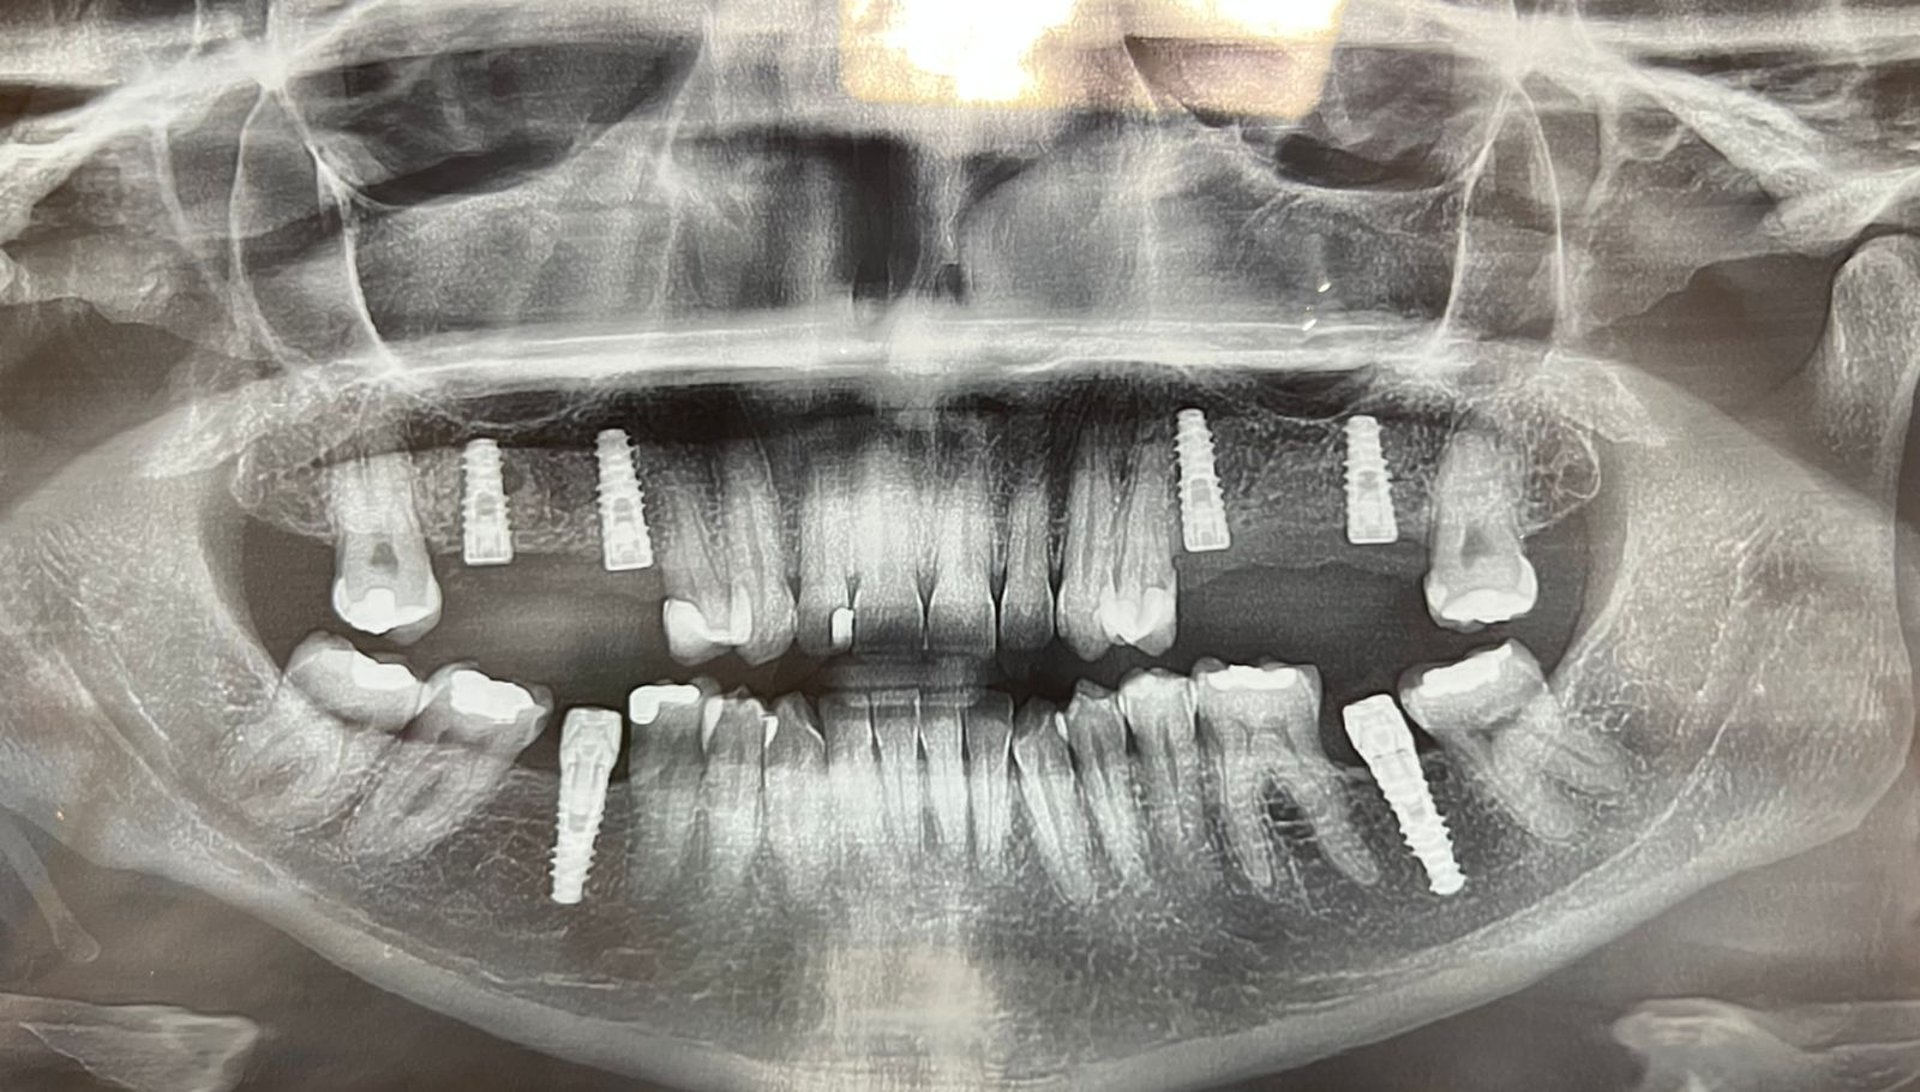

Implantes e reabilitação oral com cuidado e precisão

Mais de 1.000 sorrisos renovados

Mais de 1.000 sorrisos transformados com cuidado e precisão.